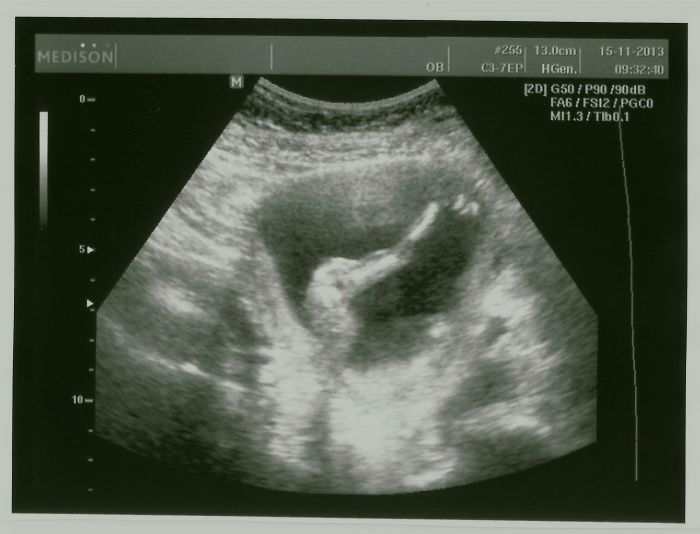

Tak jsem zpátky z kontroly a ultrazvuku :) Konečně jsem zase klidná, že je všechno tak, jak to být má

Škoda jen, že nemá pí doktorka lepší ultrazvuk, co to bude ještě nevíme. Dneska začínáme 16. týden (14+6) a naše malé bude asi akrobat, předvedl stoj na hlavě a něco jako svíčku

Má se čile k světu, huráááá. Nahraju nové fotečky až bude čas.

[389862] Jé, to je hezký, jak ho máš na těch snímcích po částech

[389976] když ono je to takové hrozně živé a neposedné mimino

Ani chvíli se nezastavilo, takže takhle po částech jsme ho stačili zachytit. Ale ten zadek s nožkama je prostě best